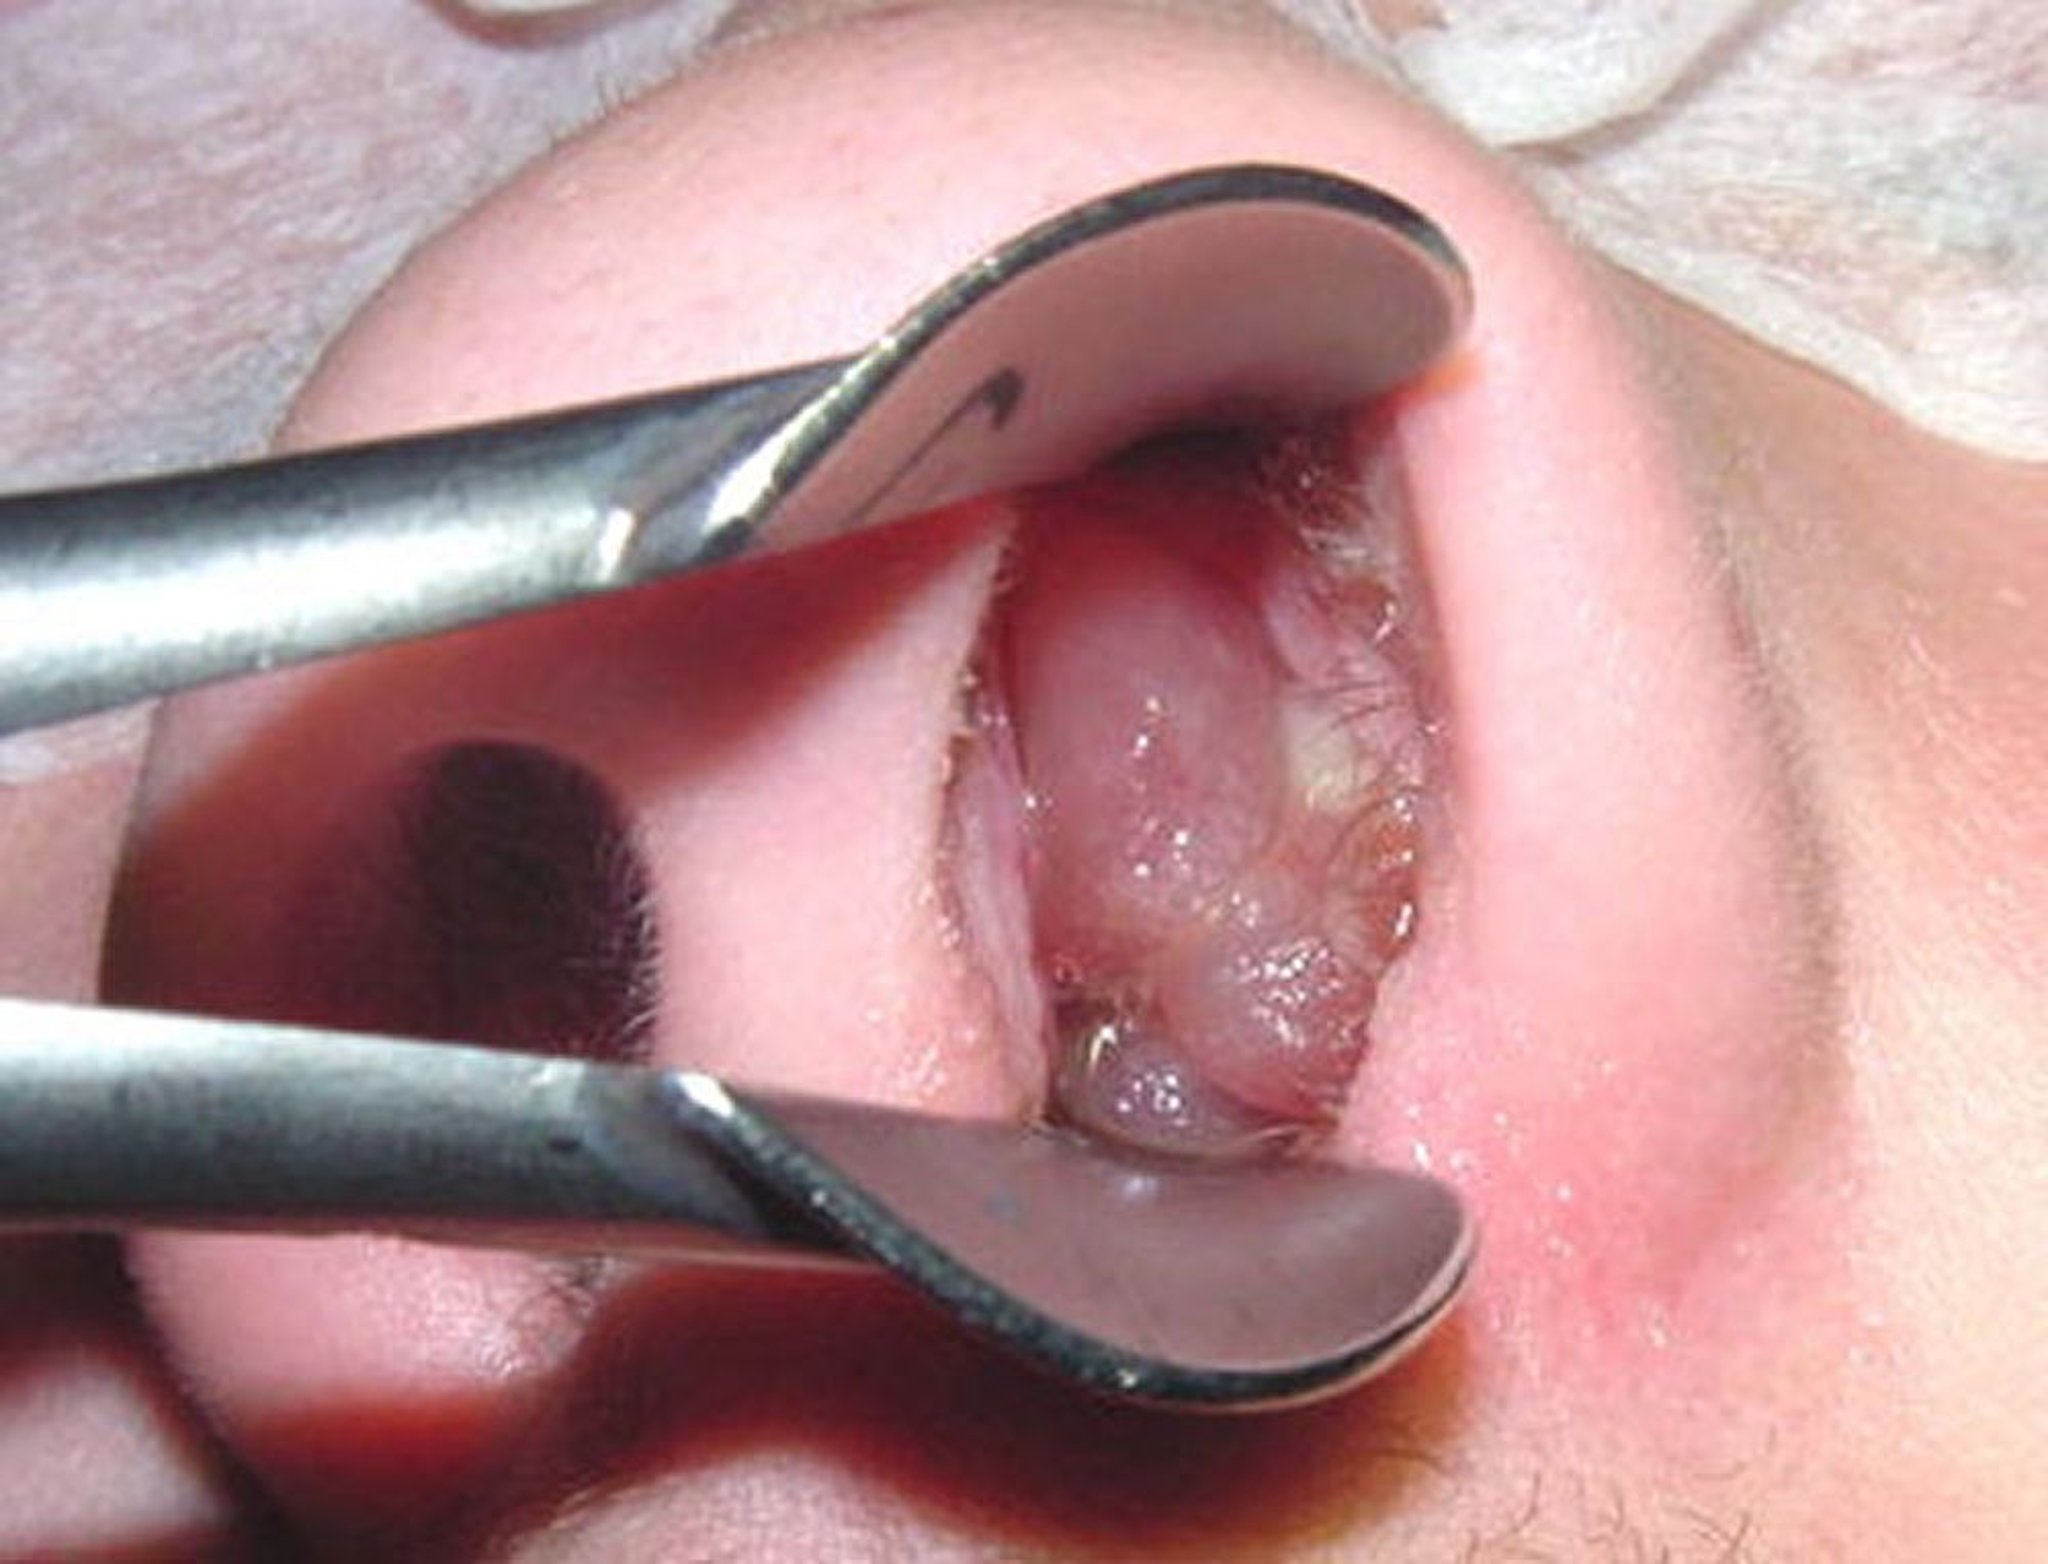

Nasaler Polyp

Ein reifer Nasenpolyp kann einer geschälten, kernlosen Traube ähneln.

Image provided by Bechara Ghorayeb, MD.